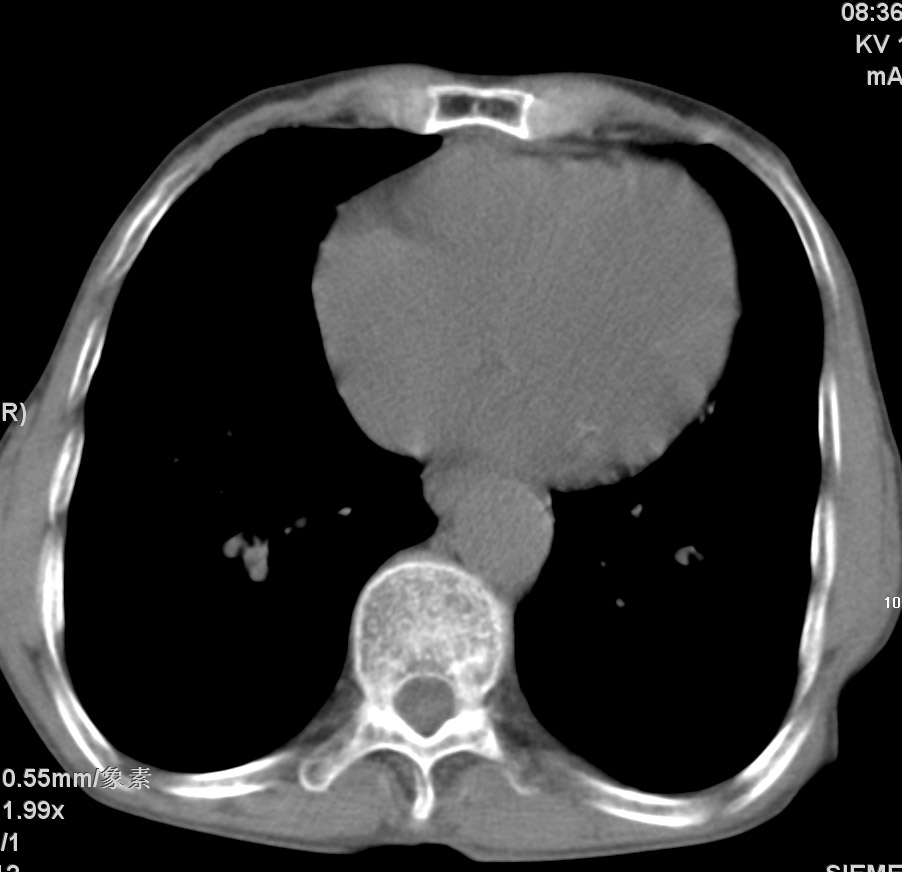

标题: CT17529:男 76 胸背部不适半月 胸透支气管炎 行CT检查 [打印本页]

标题: CT17529:男 76 胸背部不适半月 胸透支气管炎 行CT检查

意见 老年肺 少许炎症 肺大泡 右肺门略大 但支气管通畅  请各位高手指教如何下意见

支持楼主意见,右肺门略大,可能为肺动脉增粗.

慢支肺气肿,肺动脉高压.